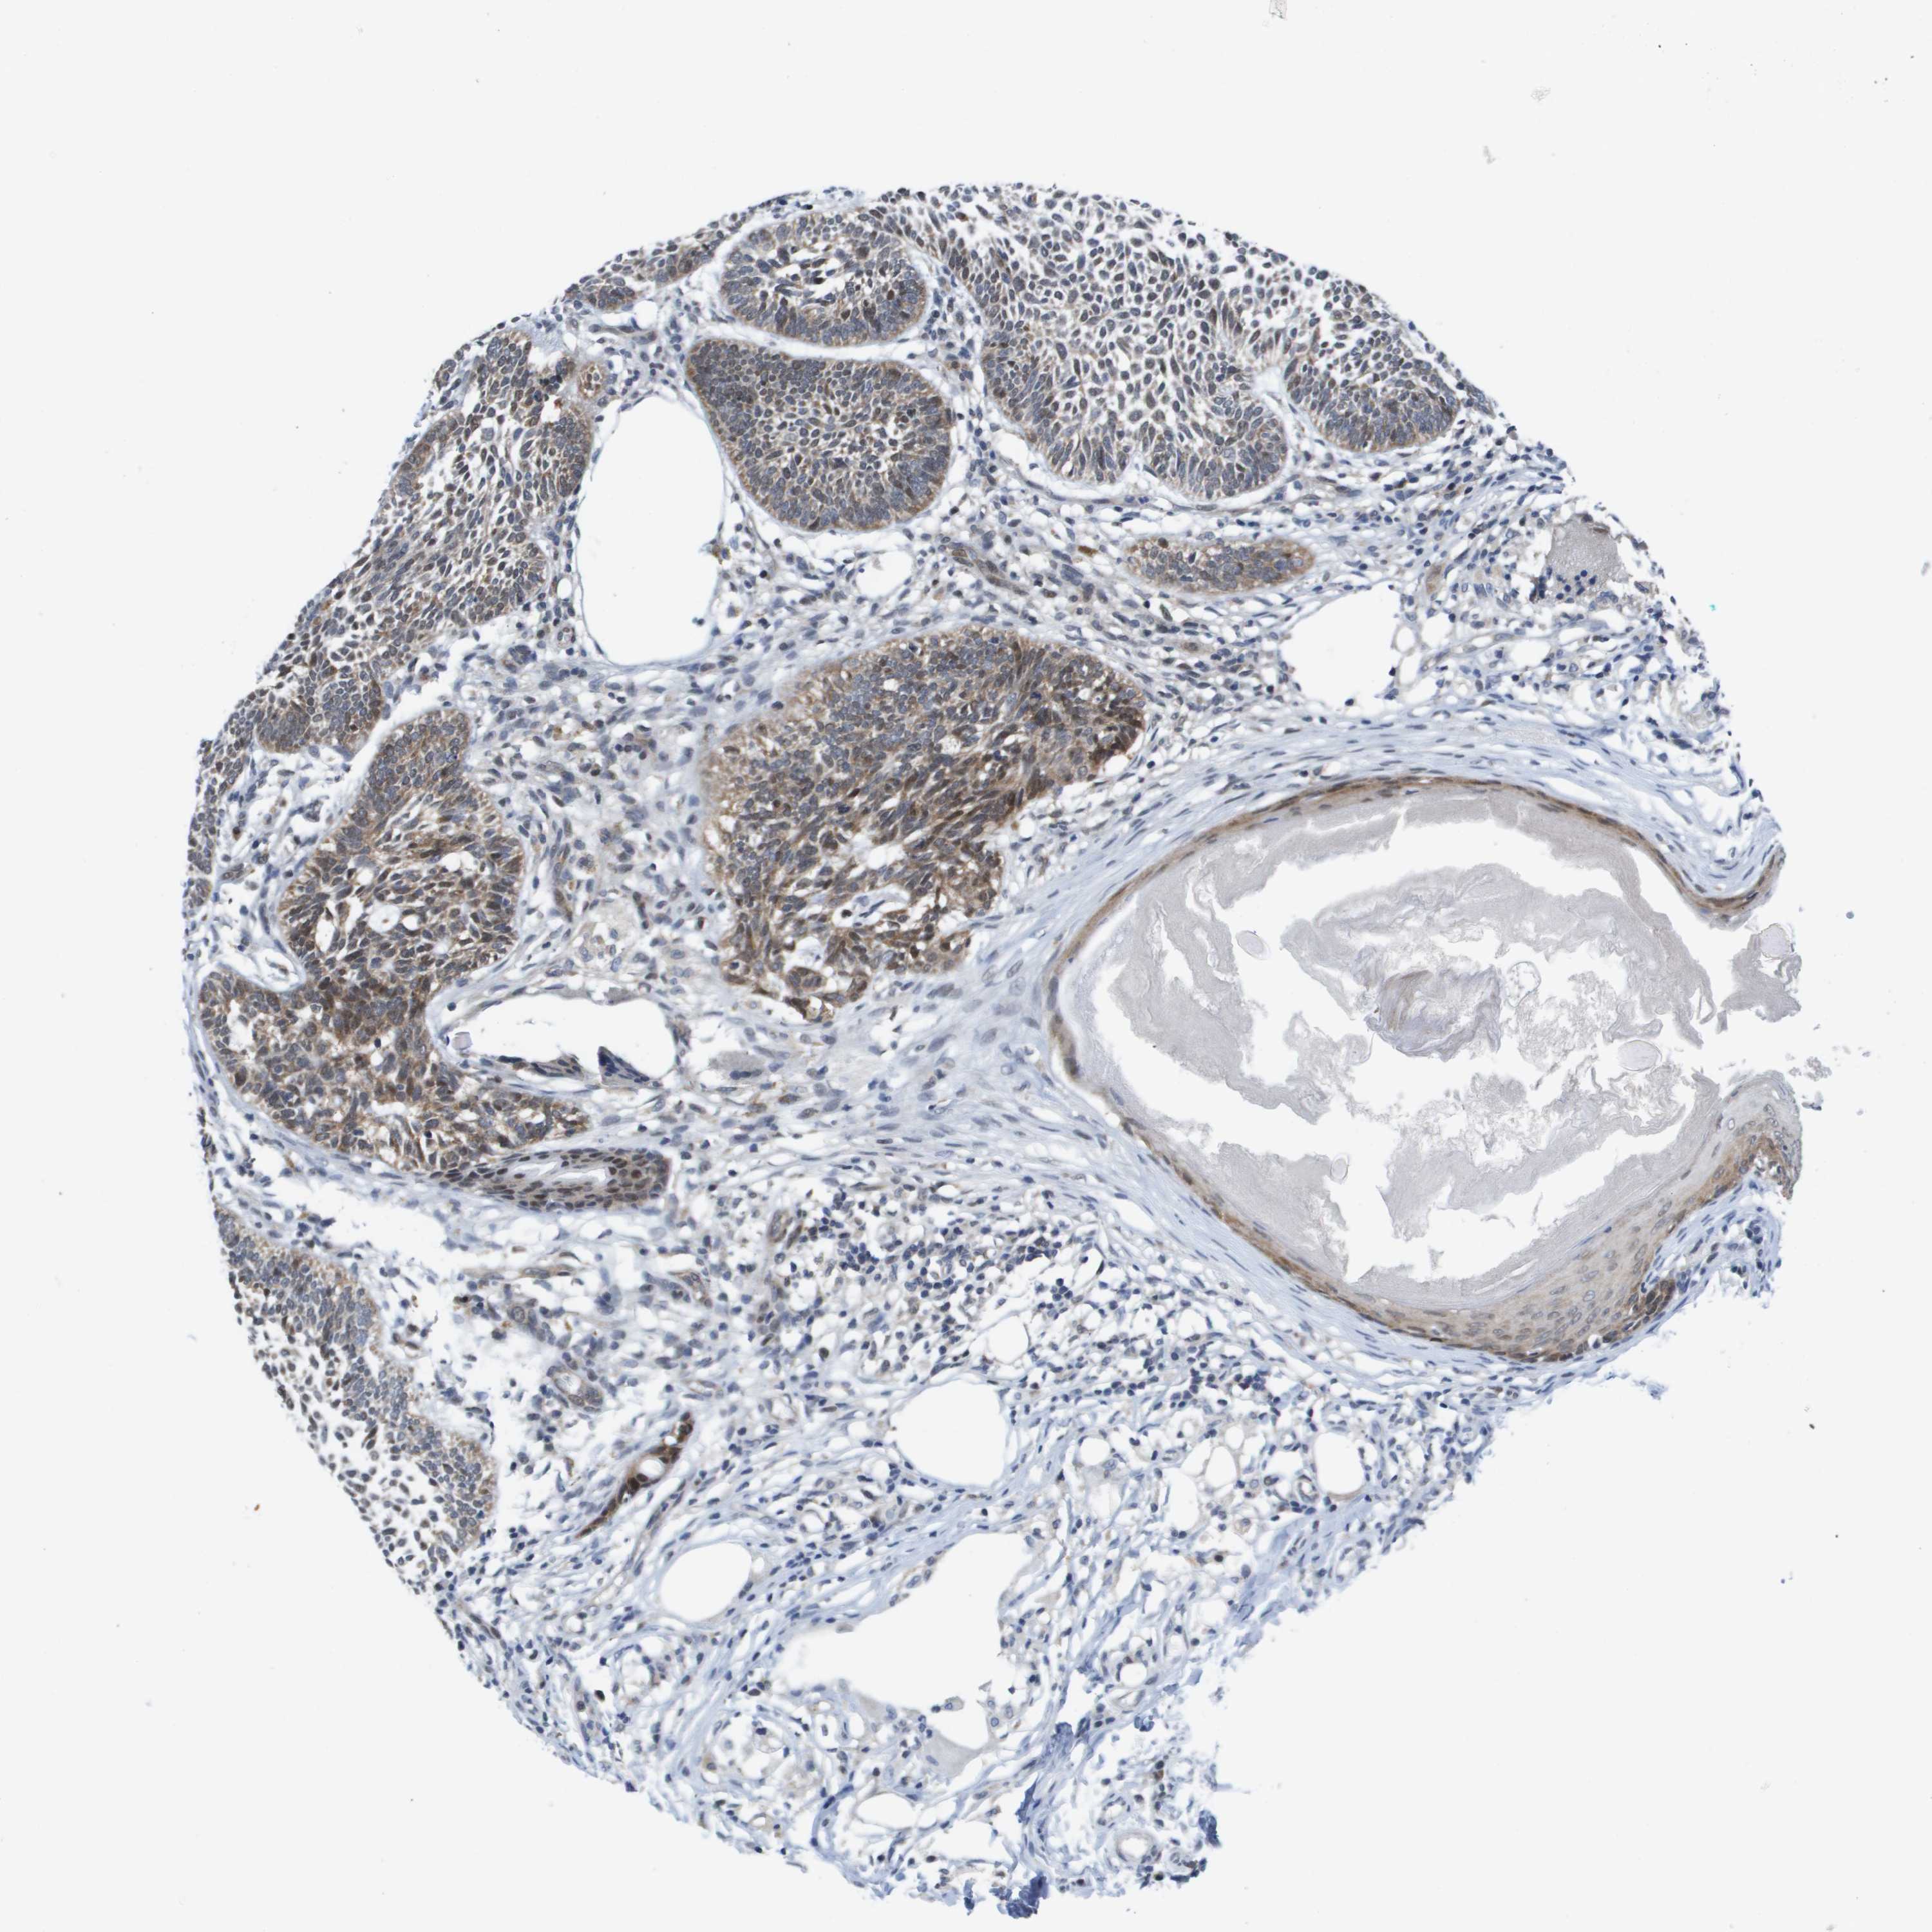

SKIN CANCER - Protein expressioni

A mouse-over function shows sample information and annotation data. Click on an image to view it in a full screen mode. Samples can be filtered based on level of antibody staining by selecting one or several of the following categories: high, medium, low and not detected. The assay and annotation is described here.

Each image is clickable and will lead to virtual microscopy that enables deeper exploration of all samples and also displays staining intensity scores, fraction scores and subcellular localization as well as patient and tissue information for each sample.

Antibody HPA006148

Antibody HPA062857

Staining

Low

Weak

<25%

Location

Cytoplasmic/membranous

Basal cell carcinoma